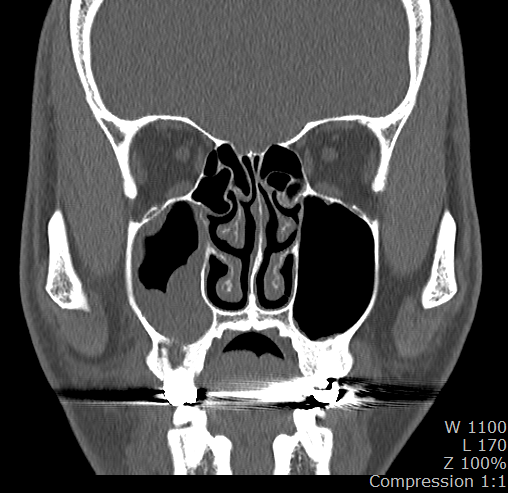

3. 파노라마나 CT를 보면 16번 치아 뿌리쪽과 부비동쪽 둥그런 구조물 사이가 검게 음영이 생겨 있는데 이게 구조물의 영구적 손상이 있는 걸까요? 아니면 치료 후에 다시 회복되는 걸까요?

23년 5월 부비동CT

-저부위는 염증때문에 펴가 녹아서 나타나는 부분으로 발치후 어느정도 기다리면 뼈가 차긴찹니다.